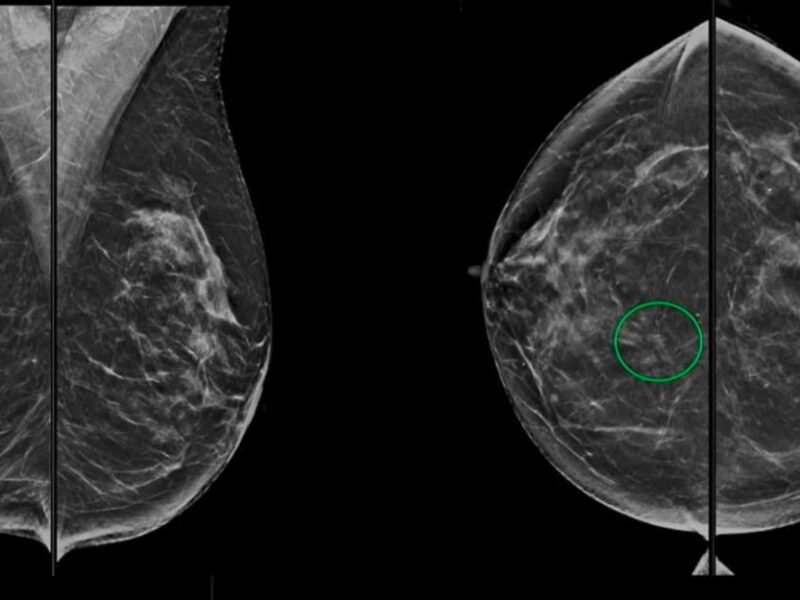

La HAS s'est globalement positionnée en faveur de la réalisation de biopsies ciblées. Cette dernière doit toutefois s'effectuer dans un cadre précis. (image d'illustration). © Carla Ferrand